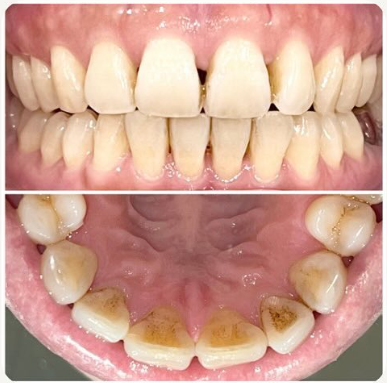

前歯の審美修復

臼歯の審美修復

歯の着色、ステイン除去